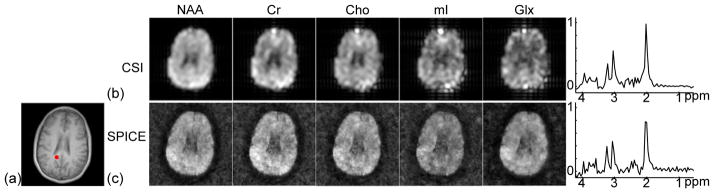

Figure 7 shows metabolite concentration maps and representative spectra obtained by the conventional CSI method and SPICE (with almost equivalent acquisition time). The metabolite concentration maps were obtained by taking the integral of the magnitude of spectra in different ranges: 2.01±0.1 ppm for NAA, 2.40±0.1 ppm for Gln+Glu (Glx), 3.03±0.1 ppm for Cr, 3.20±0.1 ppm for Cho, and 3.60±0.1 ppm for mI. The metabolite concentration maps of the CSI dataset were zero-padded to the same matrix size of the SPICE reconstruction for comparison. As can been seen, the metabolite concentration maps obtained by the conventional CSI method (Fig. 7b) have significant blurring artifacts, while SPICE achieved both high spatial resolution and good SNR (Fig. 7c).

Figure 7.

SPICE reconstruction from a nuisance signal removed short-TE SPICE dataset. (a) Reference anatomical image. (b) Metabolite concentration maps and a representative spectrum obtained from a CSI dataset (20 ms TE, 24×24 spatial encodings, 9.2 mm nominal in-plane resolution, 15.4 min scan). (c) Metabolite concentration maps and a representative spectrum (real part) obtained by SPICE (20 ms TE, 110×110 spatial encodings, 2 mm nominal in-plane resolution, 15.5 min scan).